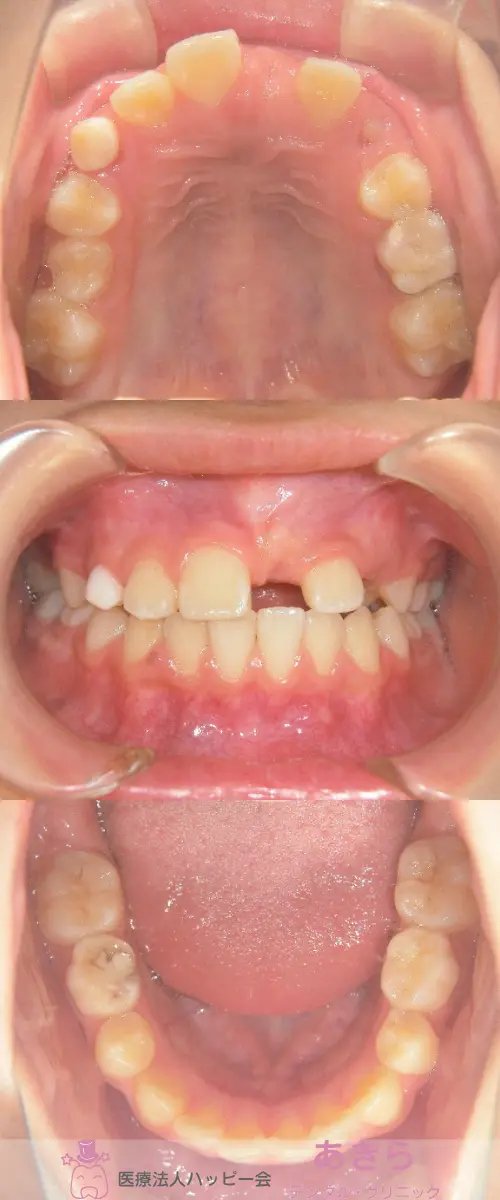

2019年4月6日 初診時口腔内写真

※経過…┗1番開窓&牽引(2019年)